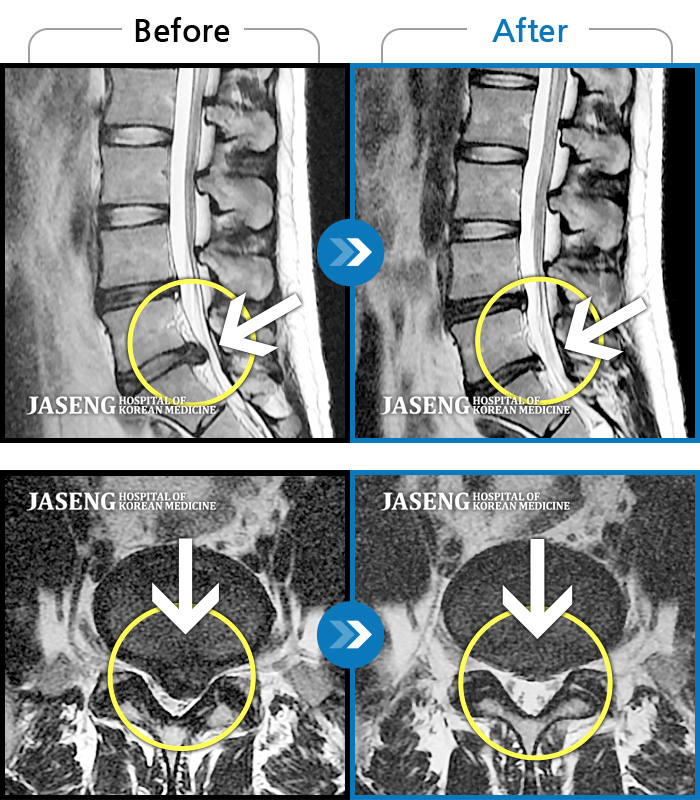

Before

After

환자에게 사전 동의를 받아 동일 조건에서 촬영되었습니다.

개인에 따라 치료 후 부작용이 발생할 수 있으니 의료진과 상담 후 치료를 진행하시기 바랍니다.

허리디스크로 옆으로 쪼그려 누워서 내원

허리, 골반, 우측 다리 통증, 야간통